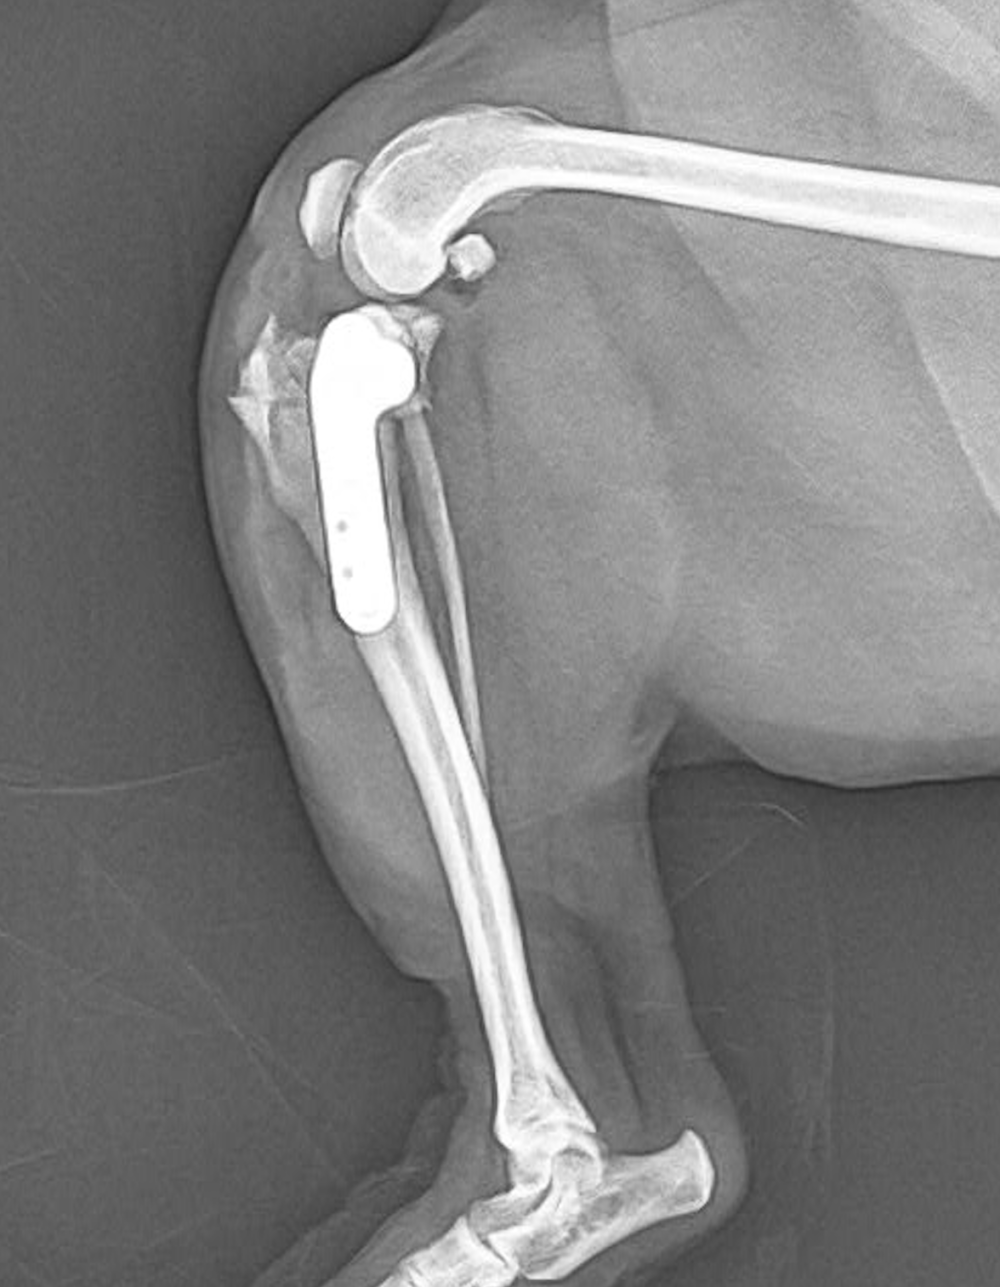

5歳チワワ

3年前に他院にてパテラのope済み

2.3日前から左後肢痛がる、着かないで歩いているとのことで来院されました。

各種検査から前十字靭帯断裂として手術を行いました。

術後1週間程度で問題なく歩けるようになりました。